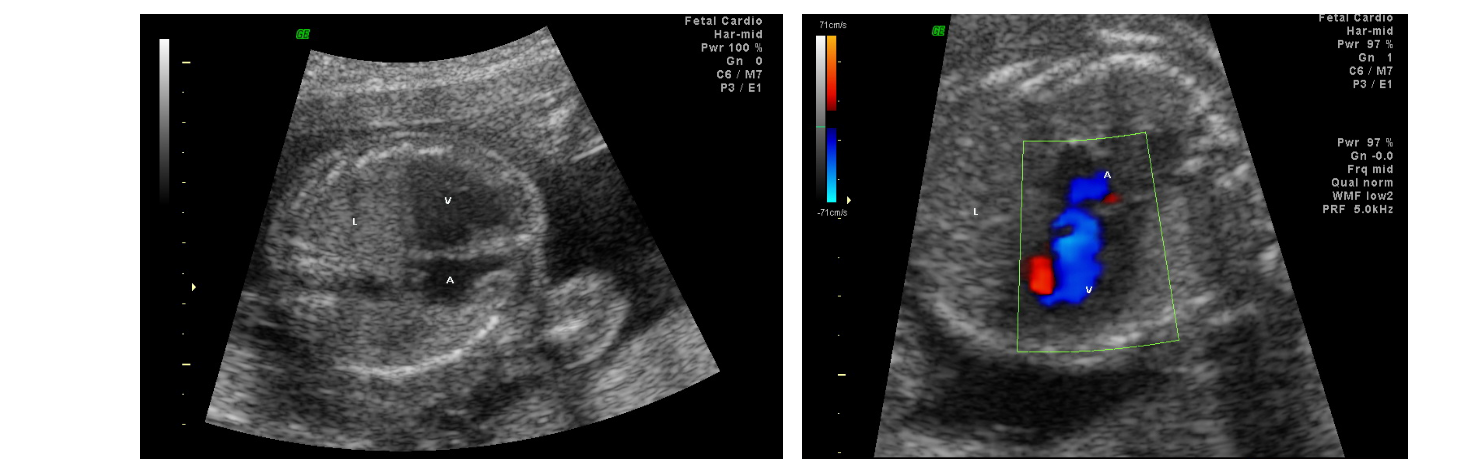

胎儿先天性畸形的超声诊断

• 4.6 胎儿先天性畸形的超声诊断